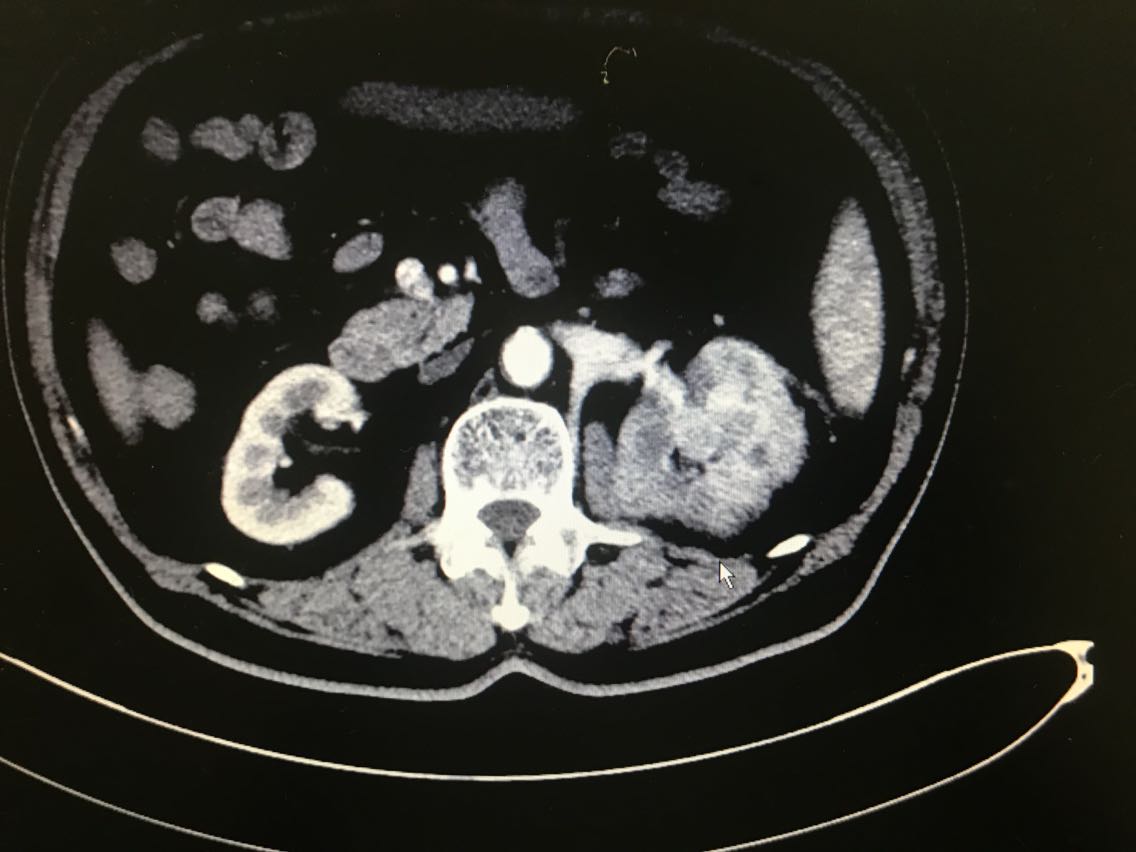

患者男性,81岁。 主诉:血尿伴左侧腰痛一月余 现病史:患者一月前出现血尿,伴左侧腰痛,于当地医院就诊,诊断为左侧肾盂占位。患者为求进一步治疗来我院门诊,门诊以肾盂恶性肿瘤收入院。起病以来,患者睡眠饮食尚可,二便无明显改变,体重未减。 既往史无特殊。

查体无特殊。 辅助检查: 全腹CT示:左肾上极肿块,侵犯左肾上盏并突入左肾盂,性质:左肾细胞癌可能性大,肾盂癌待排,结合临床。

诊断:左肾占位:肾盂癌? 治疗:腹腔镜左肾盂癌根治术